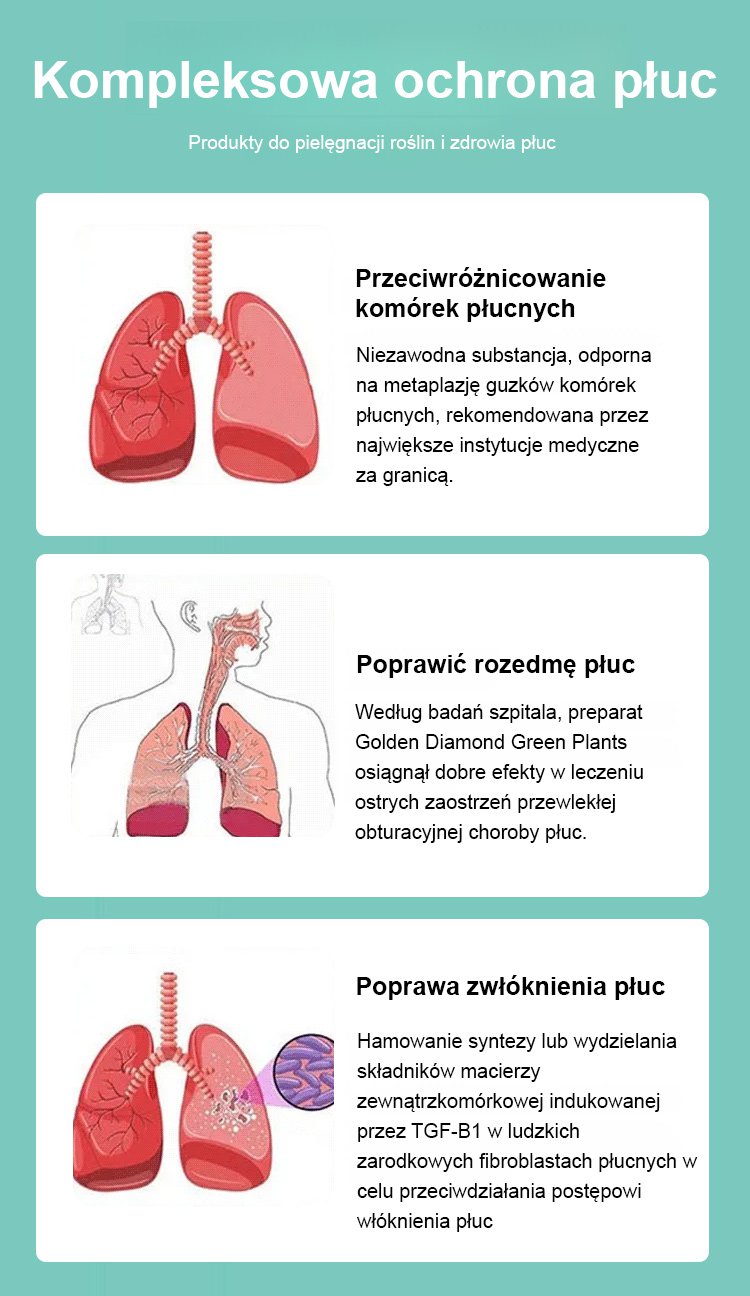

Złoty diament rośliny zielone【Król uzdrawiania płuc】

Złoty diament rośliny zielone【Król uzdrawiania płuc】